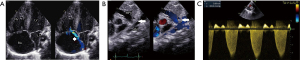

The first case concerns a female neonate born at term (39+5/7 weeks of gestation) in a context of oligohydramnios and cardiac rhythm abnormalities leading to immediate delivery. The mother, aged 33 years, had not been exposed to NSAIDs or to other potential risk factors throughout her pregnancy. Fetal ultrasounds performed at 13- and 20-weeks of gestation were normal. The immediate clinical picture at birth included respiratory distress and hypoxemia. Emergency echocardiography (delivery room) revealed moderate RV dilatation with signs of severe suprasystemic PPHN and RV dysfunction (Figure 1). In addition, the tricuspid valve and pulmonary valve appeared dysplastic, with mild to moderate regurgitation. The foramen ovale was widely patent with an exclusive right-to-left shunt, while the DA was completely closed. Chest X-ray showed mild cardiomegaly and right pneumothorax without mediastinal shift. The baby started receiving inhaled nitric oxide (iNO) at 20 ppm using only a high-flow nasal cannula (FiO2 0. 8). A continuous intravenous infusion of milrinone was also started at 0. 5 mcg/kg/min. The outcome was favorable with weaning from iNO on the second day and discontinuation of milrinone on the fourth day. The child was started on oral sildenafil (2 mg/kg/day) and follow-up echocardiograms showed a gradual decrease in pulmonary pressure with normalization of RV function. The patient was discharged from the hospital on day 9, while still on sildenafil. She was successfully weaned off the medication five months later, and repeated echocardiograms showed normal pulmonary pressure (Figure 2) VSports最新版本. At 1 year of age, she remained asymptomatic, with good neurological development and normal RV systolic pressure of 24 mmHg.

In this setting of suggestive hemodynamic compromise, an emergency cesarean section was indicated, at birth, the newborn immediately presented with respiratory distress without abnormalities on chest X-ray, while transthoracic echocardiography performed within 10 minutes of life confirmed closure of the DA. There was an exclusively right-to-left shunt through the foramen ovale. The RV was severely hypertrophic, slightly dilated and dysfunctional. The tricuspid valve was confirmed as dysplastic with moderate regurgitation and signs of suprasystemic pulmonary hypertension (Figure 4).